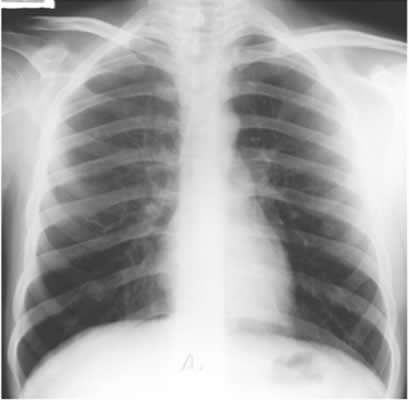

Answer: Yes. You must make sure that the film has been taken in full inspiration, as shown in this image.

At least six ribs should be visible anteriorly and 10 ribs posteriorly.

An expiratory film can look very abnormal.

These two films were taken seconds apart.